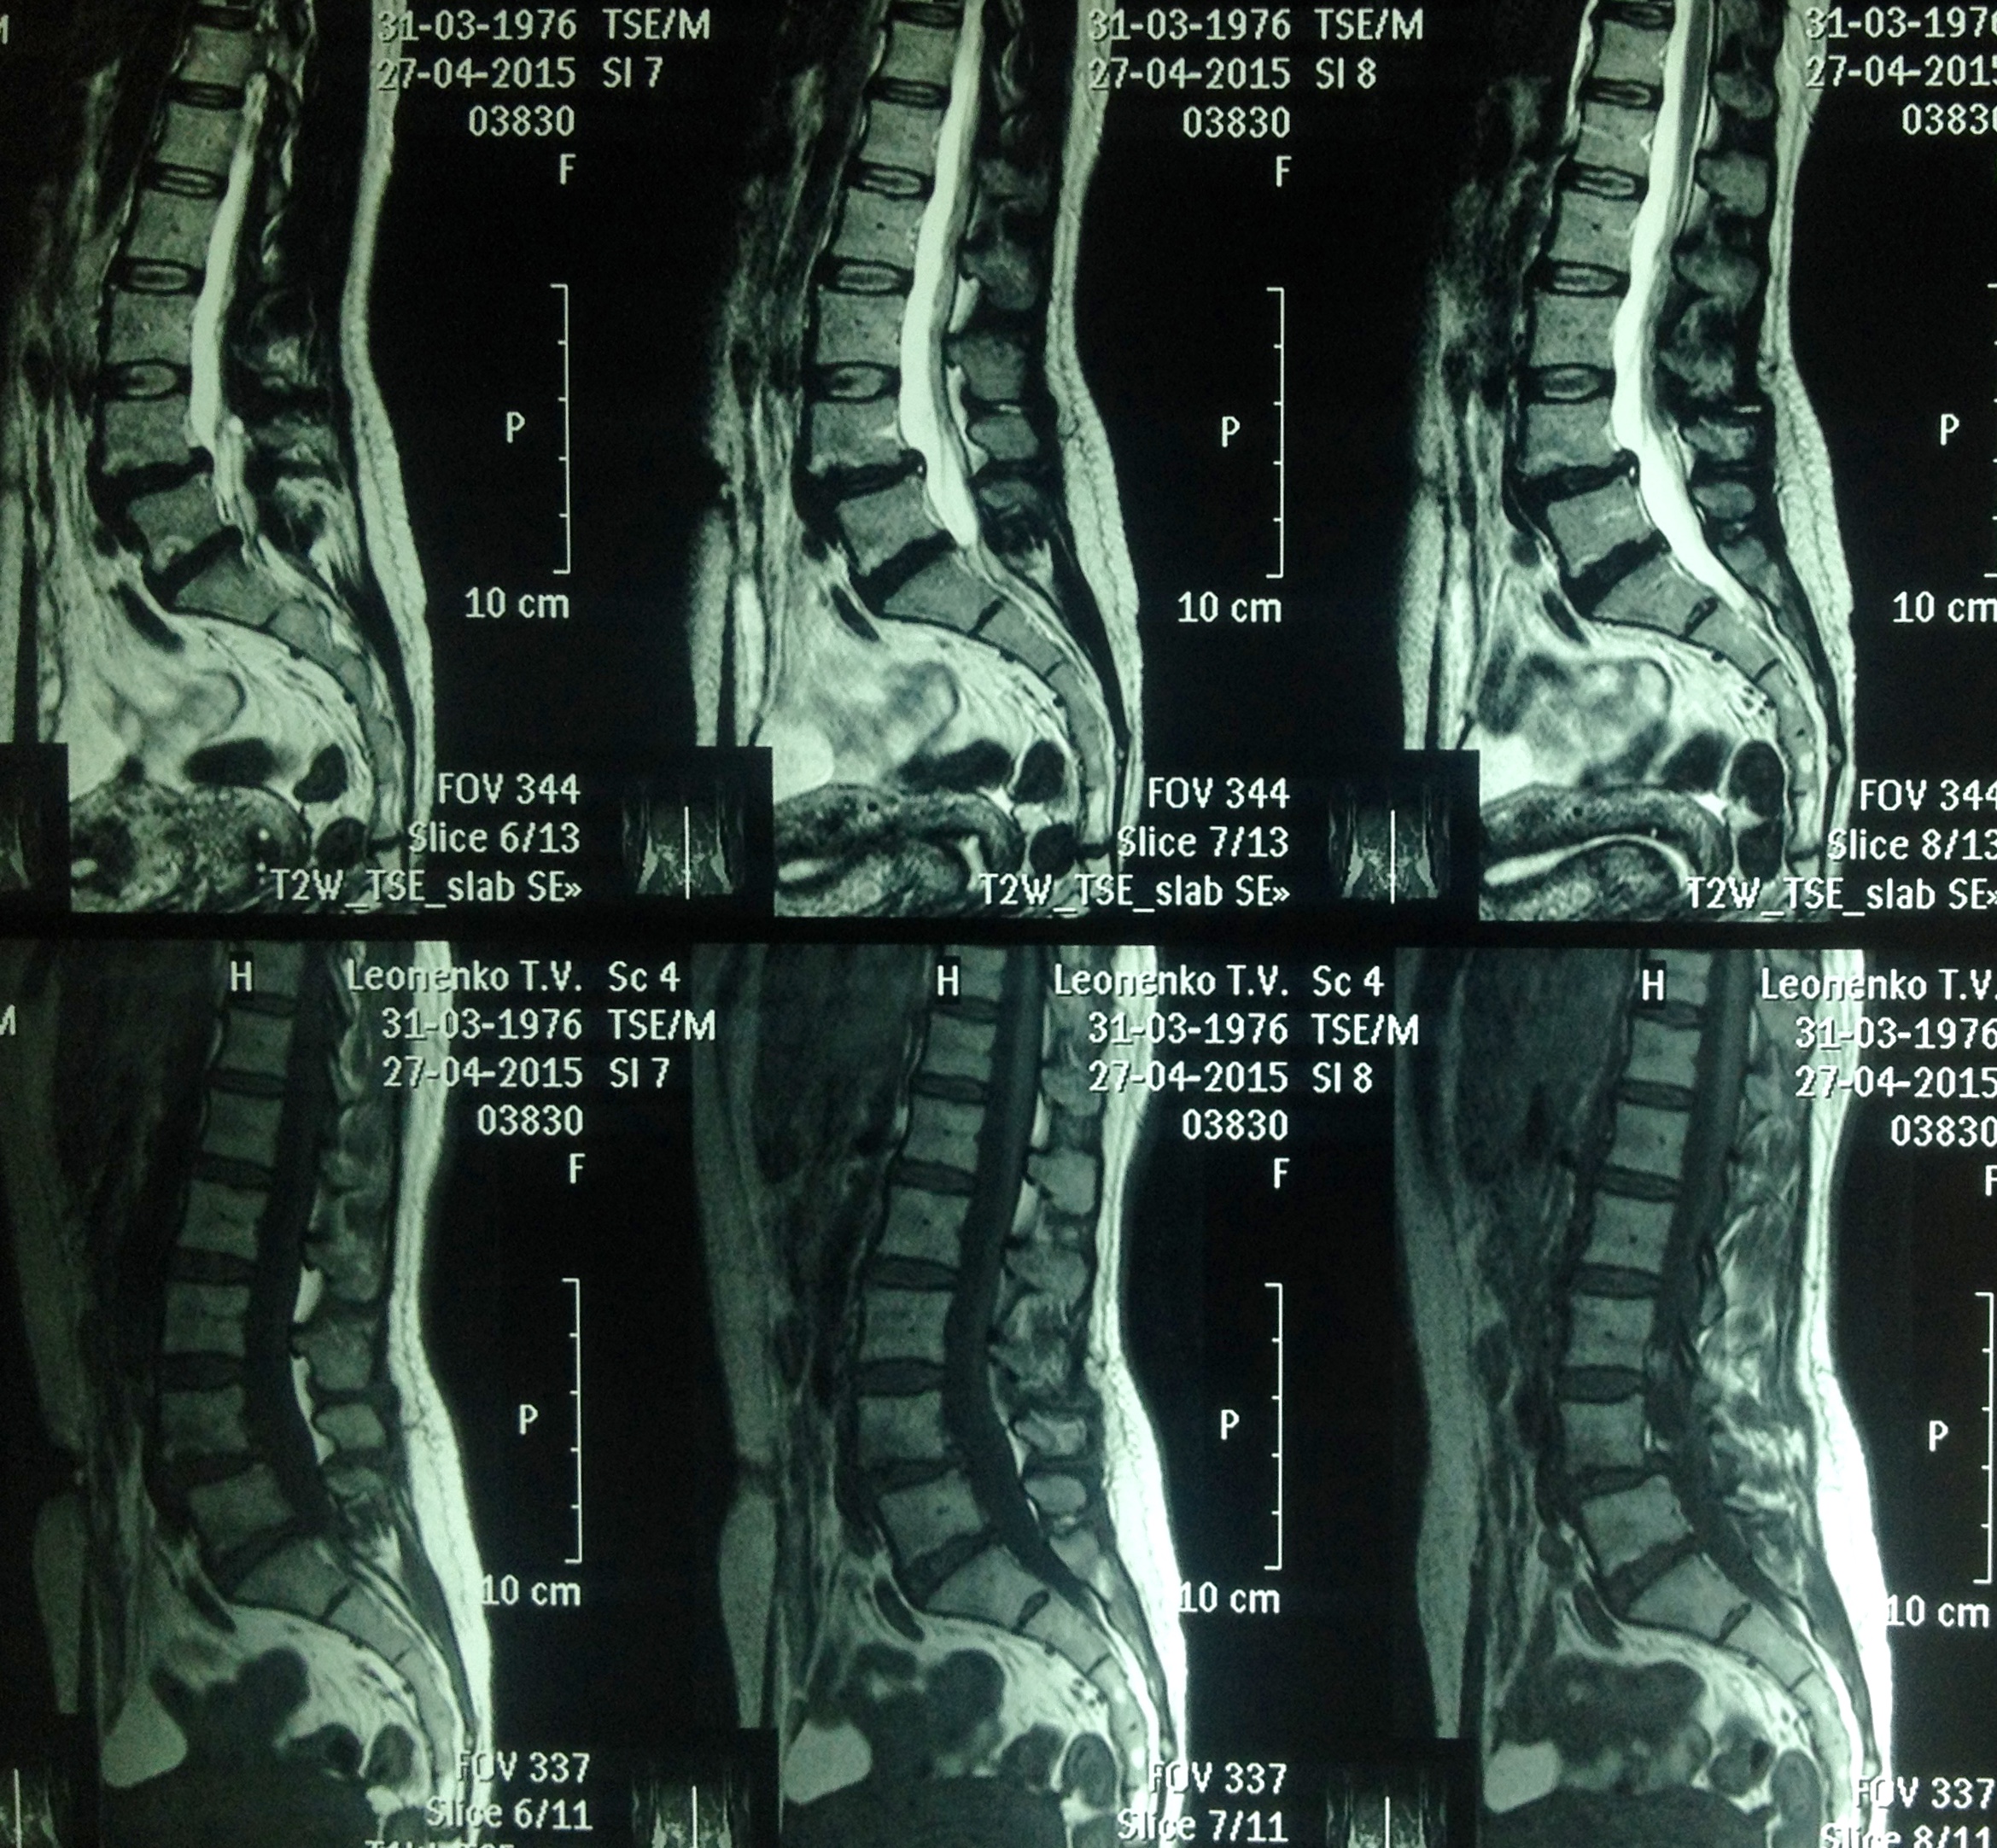

Спондилолістез (від грец. Spondylos – хребець і listhesis – зміщення, зісковзування) – це патологія хребта, при якій один з хребців (нижчележачий) зміщується вперед, назад або в бік по відношенню до інших (вище) хребців.

У більшості випадків допереду зісковзують четвертий або п’ятий поперековий хребець, інша локалізація зустрічається набагато рідше. На сьогоднішній день виділяють п’ять основних варіантів поперекового спондилолістезу: диспластичний (вроджене захворювання), істмічний (спондилоліз, особливо поширений серед осіб, які займаються спортом і виконують рухи з перерозтягуванням, тобто гімнастів, регбістів тощо), дегенеративний (частіше у дзвінок на частіший). травматичний (внаслідок прямої травми або при пошкодженні хребців) та патологічний (через дефект у кістці, викликаний пухлиною).

Значне зміщення однієї з хребців обумовлює звуження хребетного каналу, у результаті може наступити здавлення чи спазм артерії і порушення кровопостачання спинного мозку. Наприклад, під час бігу це спровокує настання різкої слабкості в ногах і людина впаде, ніби підкошена, але після відпочинку скарги нівелюються. Може статися і здавлення безпосередньо самого спинного мозку, що тягне у себе ослаблення чи відсутність здатності довільно рухати нижніми кінцівками і порушення функції тазових органів (втрата контролю над роботою сечового міхура, кишечника). Змінюється і хода. Діагноз встановлюють виходячи з даних рентгенологічного дослідження хребта.